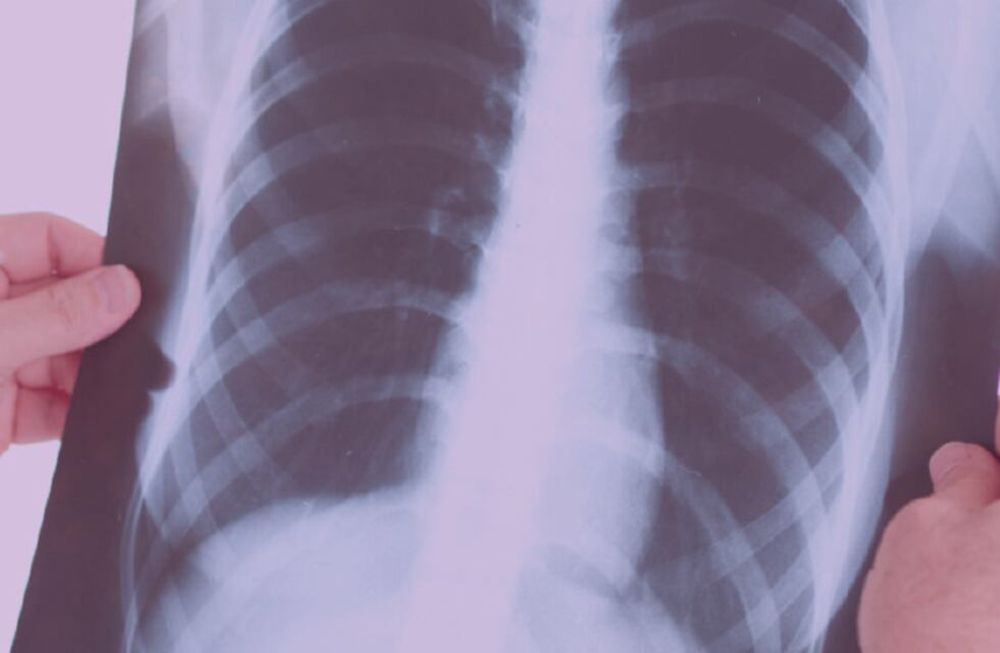

Si bien la clínica es muy orientadora, el diagnóstico es mediante una radiografía de tórax, imprescindible para el diagnóstico y también para conocer la extensión de la infección.